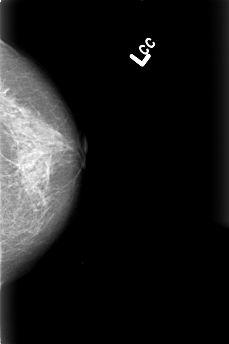

B_3016_1.LEFT_CC

LEFT_CC LINES 4464 PIXELS_PER_LINE 2968 BITS_PER_PIXEL 12 RESOLUTION 50 NON_OVERLAY